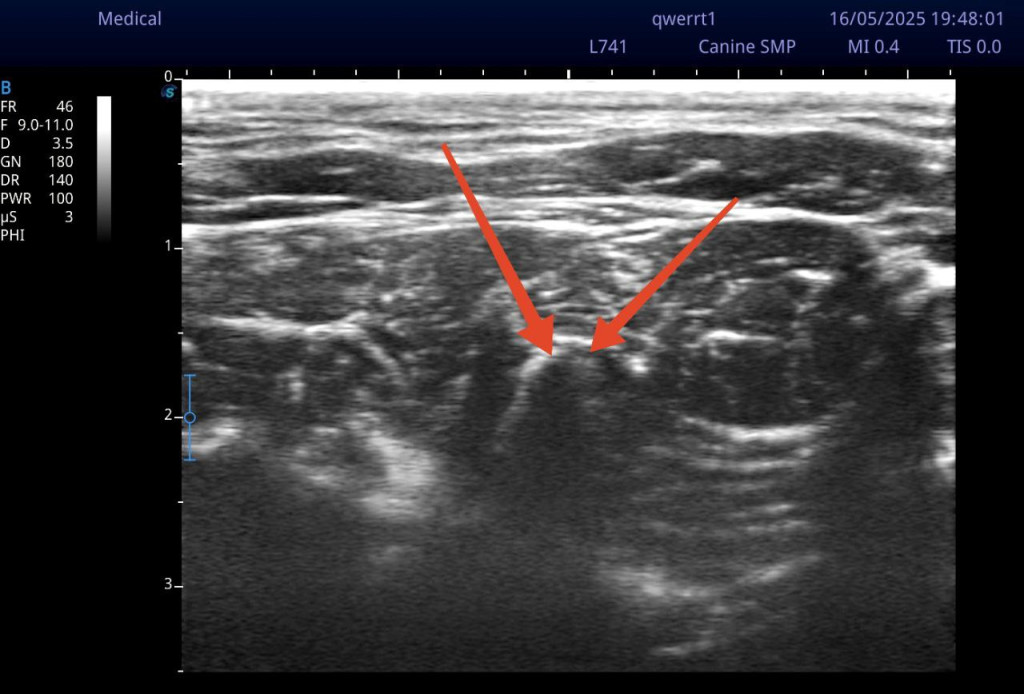

Для выполнения данной хирургической манипуляции, помимо общей анестезии, индуцированной пропофолом и поддерживаемой ингаляционной анестезией с помощью изофлурана, была проведена блокада лестничной мышцы под контролем УЗИ (видео 2). Техника выполнения блокады лестничной мышцы схожа с методикой блокады длинной мышцы головы за исключением необходимости идентифицировать четвертый шейный позвонок с краниальной его части, при этом целевой точкой будет вентральный бугорок поперечного отростка С4. Он визуализируется как акустическая тень от кортикального слоя вентрального бугорка, направленная перпендикулярно к поверхности сканирования. Над бугорком определяется структура, напоминающая «шапочку», которая является лестничной мышцей.

Возможны два подхода к проведению блокады (рис. 9). Введение спинальной иглы может осуществляться с дорсальной или вентральной стороны датчика. При первом подходе игла направляется до соприкосновения с вентральным бугорком между вентральной частью лестничной мышцы и длинной мышцей головы. Введение местного анестетика в этой зоне предполагает более вентральное его распределение. При втором подходе, когда игла направляется с дорсолатеральной поверхности шеи, точкой введения анестетика будет дорсальная часть лестничной мышцы рядом со средними межпоперечными мышцами. При выполнении такой инъекции на УЗИ можно обратить внимание, как анестетик стекает в сторону, к месту выхода спинномозгового нерва из межпозвоночного отверстия. На рис. 10 красной точкой отмечено место введения анестетика на КТ-скане третьего шейного позвонка.